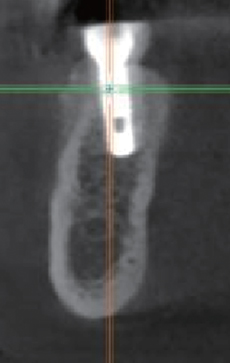

#45 Implant 식립

#47 Implant 식립

수술 후 파노라마